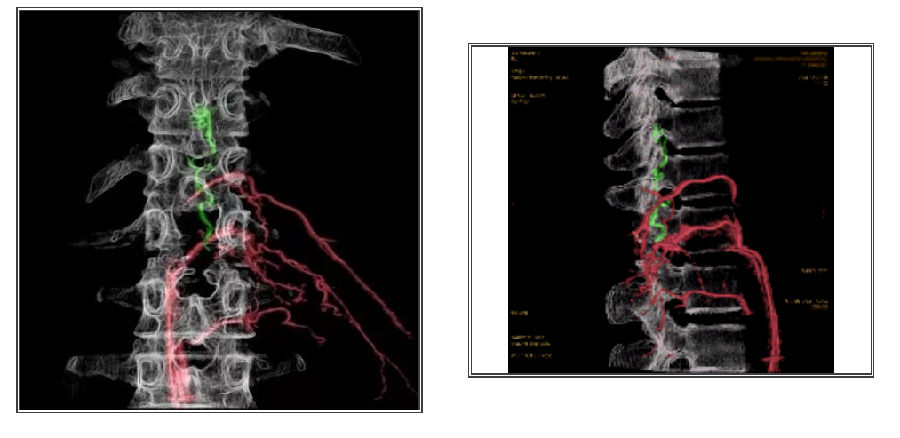

影像融合技术在脑脊髓血管病中探索及创新